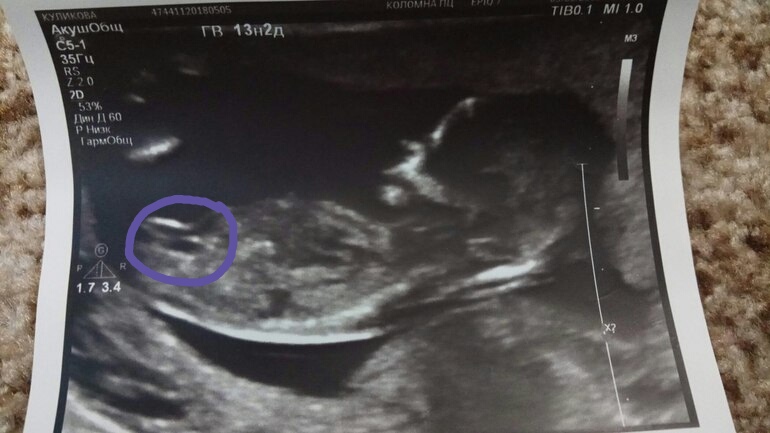

если я правильно поняла это вот половой бугорок?)

Девочка девочка))) у нас так же на УЗИ)) посмотрите у меня

Мальчик у вас?у вас на мой взгляд так же как у меня, просто у меня УЗИ прям крупным планом и близко, у всех в основном как у вас , подальше, и малыш поменьше)

Так же как и у меня , я имею ввиду расположение)

Пока вроде мальчик) не, ну если у вас на фото половой бугорок то это точно девочка.

Ну у вас вроде тоже этот бугорок видно в том же месте что и у меня, только он прям к верху поднят)) а вам врач сказал что мальчик?

хм) а я вот не видела еще у вас в профиле что мальчик, по фото узи сразу подумала что мальчик)) я думаю это тот самый бугорок) с градусом как у мальчика))

Нет, врач ничего не сказала, не потому что не видит, а потому что противная))) поликлиника бесплатная) нечего им с нами сюсюкаться) на фото 13.1